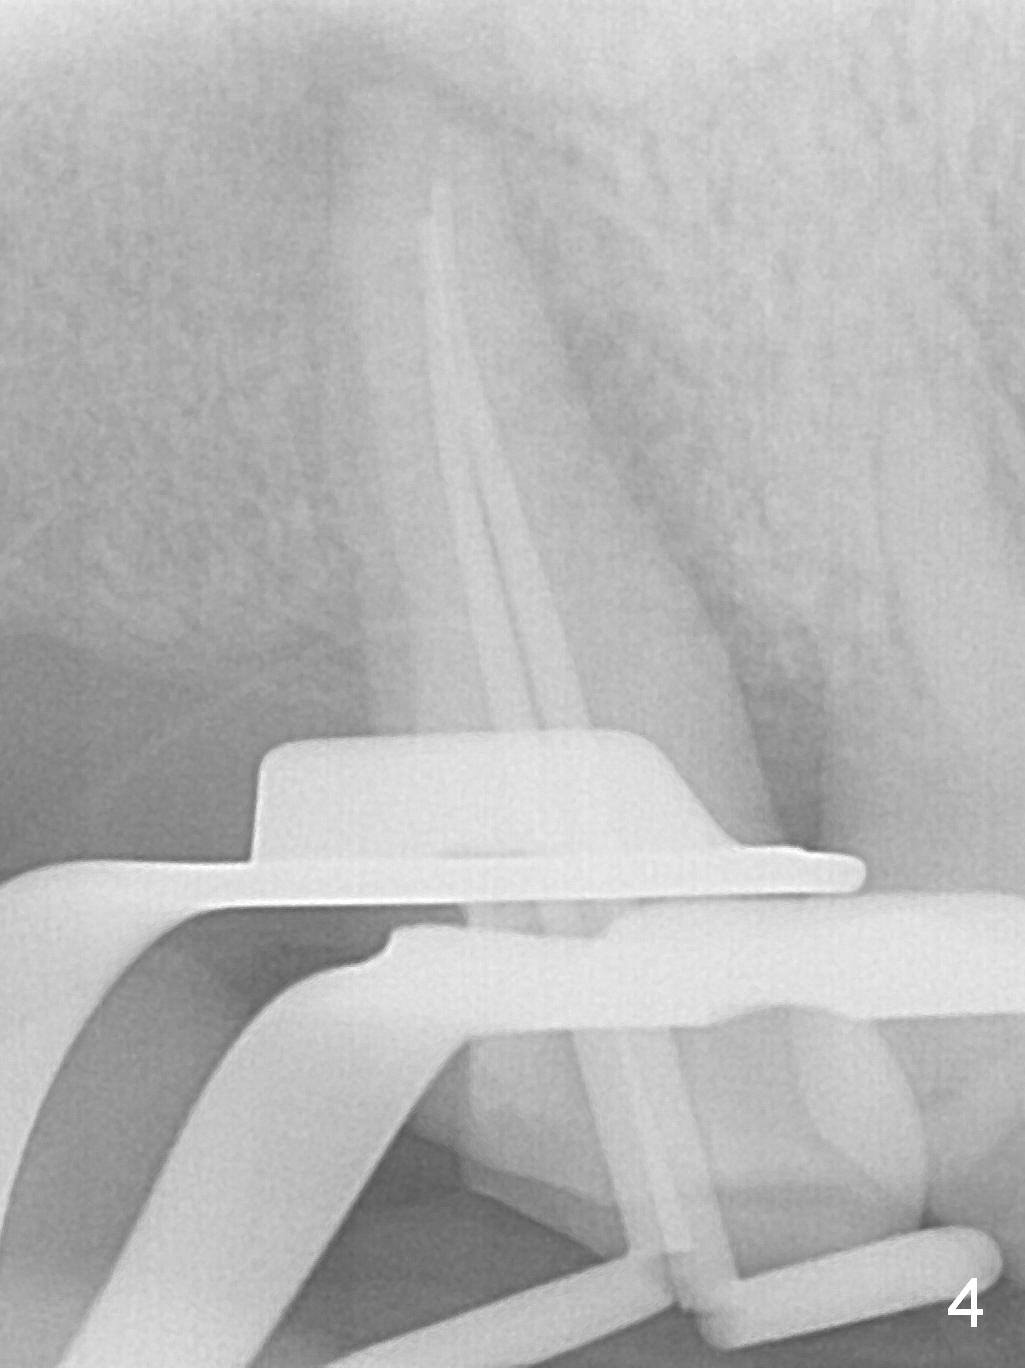

A 52-year-old woman presents to clinic with chief complaint "I can not bite in the upper right". Exam shows DO caries of the tooth #2 (Fig.1). After scaling & root planing and the tooth #1 extraction, pulpotomy is performed at #2. Two months later, pain recurs with swelling. When root canal therapy is finished at #2 (Fig.2-6), the tooth is found to have moderate mobility with guarded to poor prognosis. If the infection does not resolve, extraction and immediate implant seem to be necessary. Considering low bone density around the site of #2, a long implant is indicated (18 mm bone-level, Fig.7,8).